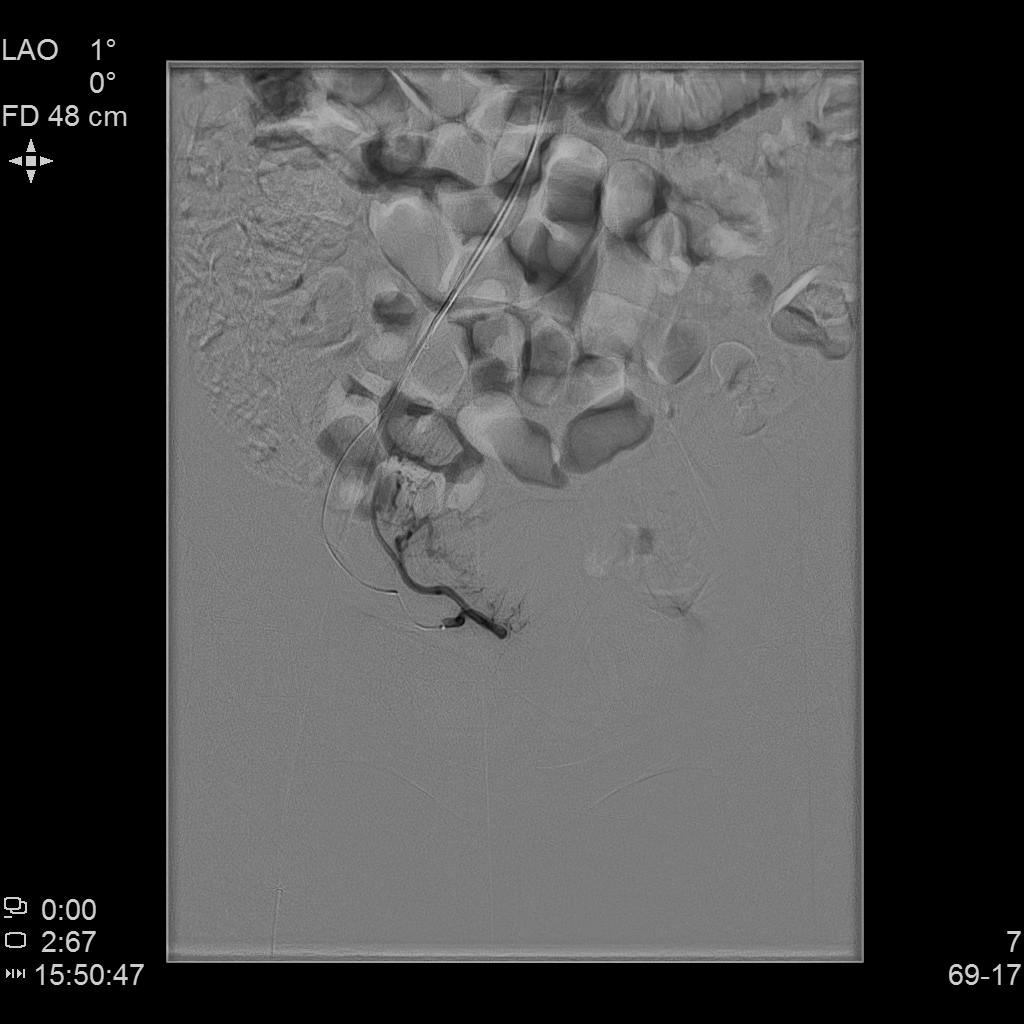

例2

中年患者,患有“子宫腺肌瘤”7年余,长期受痛经、月经量增多折磨,严重影响生活质量。经多处求医,经历药物调理、“曼月乐”宫腔植入、“海扶刀”消融术等多种治疗,痛经、月经量多等情况一直无法得到有效缓解,病情日益严重。

左侧子宫动脉造影

术后复查MRI显示子宫明显缩小,腺肌瘤明显坏死吸收